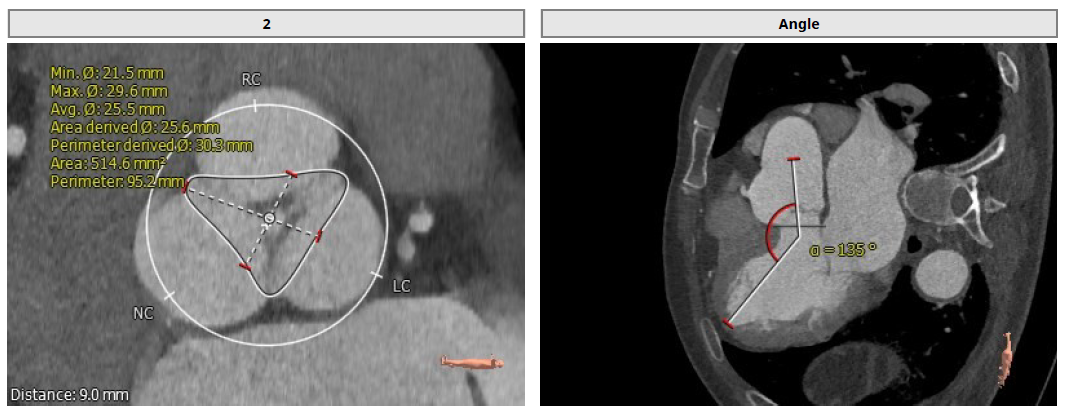

影像诊断:

1.患者主动脉瓣三叶式,瓣叶基本等大,瓣叶增厚,瓣叶未见明显钙化;

2.患者主动脉瓣环周长折算直径约30.1mm;

3.患者双侧冠脉开口高度可LCA:16.2mm,RCA:21.8mm;

4.患者术中造影角度LAO:7°,CAU:1°。

Annulus: 30.1mm

环上结构折算直径:30.3mm ;主动脉瓣环夹角:135°

左冠高度:16.2mm;右冠高度:21.8mm

LVOT: 31.5mm;窦部直径:42.7/42.0/46.9mm

窦管交界:39.9mm;升主动脉:44mm

术中造影角度LAO: 7°,Caudal: 1°